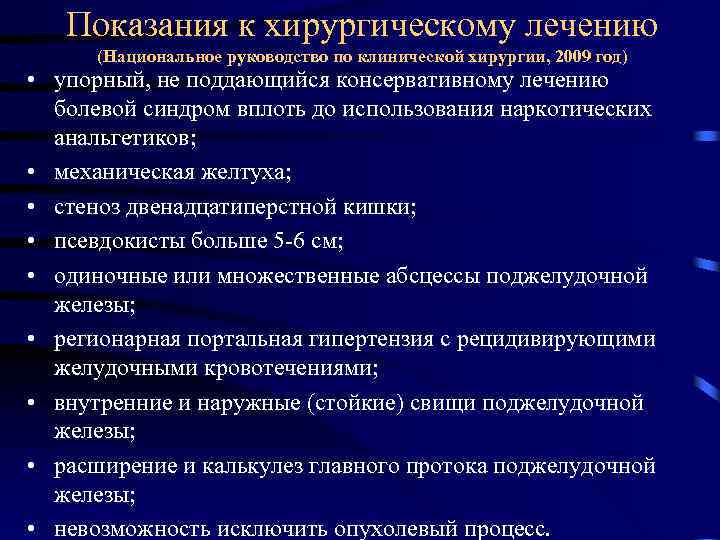

Показания к хирургическому лечению (Национальное руководство по клинической хирургии, 2009 год) • упорный, не поддающийся консервативному лечению болевой синдром вплоть до использования наркотических анальгетиков; • механическая желтуха; • стеноз двенадцатиперстной кишки; • псевдокисты больше 5 6 см; • одиночные или множественные абсцессы поджелудочной железы; • регионарная портальная гипертензия с рецидивирующими желудочными кровотечениями; • внутренние и наружные (стойкие) свищи поджелудочной железы; • расширение и калькулез главного протока поджелудочной железы; • невозможность исключить опухолевый процесс.